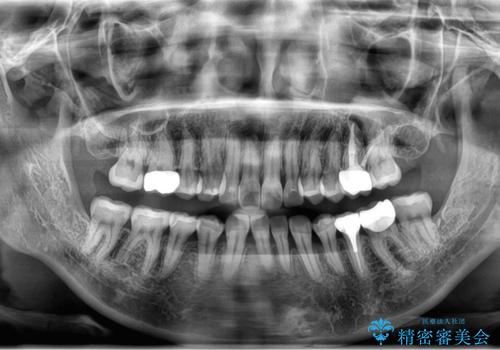

全体的な虫歯治療 銀歯をセラミックに

- 当院で矯正治療後、虫歯治療を一通り行いました。

- およそ100万円費用は治療当時の料金となります